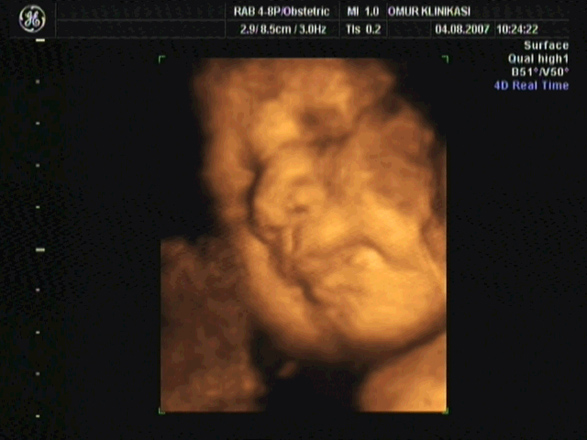

" Современные технологии не стоят на месте, постоянно проникая и обновляя различные области знаний. Не исключение и медицина, а точнее отрасль акушерства и гинекологии. Насчёт 3D УЗИ всё понятно - это получение изображения плода в 3-х мерном режиме. 4D УЗИ представляет собой новый метод исследования с помощью ультразвука, который сегодня доступен всем, в том числе и беременным, благодаря компьютерным технологиям. Что же такое 4D УЗИ? Ведь в пространстве всего 3 плоскости: горизонтальная, фронтальная и сагиттальная. А четвёртым в данном случае является - время, т.е. изображение плода даётся со скоростью 25 фотографий за 1 секунду в режиме реального времени (видеоизображение). При исследовании 4Д УЗИ можно получить более полную информацию.

Изображение 4D УЗИ позволяет рассмотреть плод в деталях. Это позволяет до родов установить прочную психоэмоциональную связь будущих родителей с ребенком. Родители не только видят своего ребенка в "объемном" виде, пересчитать пальчики на ручках и ножках малыша, рассмотреть его личико, но и могут снять видеофильм на память, записанным на различные носители.

Четырехмерное УЗИ позволяет рассмотреть мимику малыша. Будущие родители могут увидеть эмоции своего ребенка и понять, что он чувствует - улыбается, грустит, расстроен. Мимика ребенка направит врачей на наличие тех или иных проблем в его развитии.